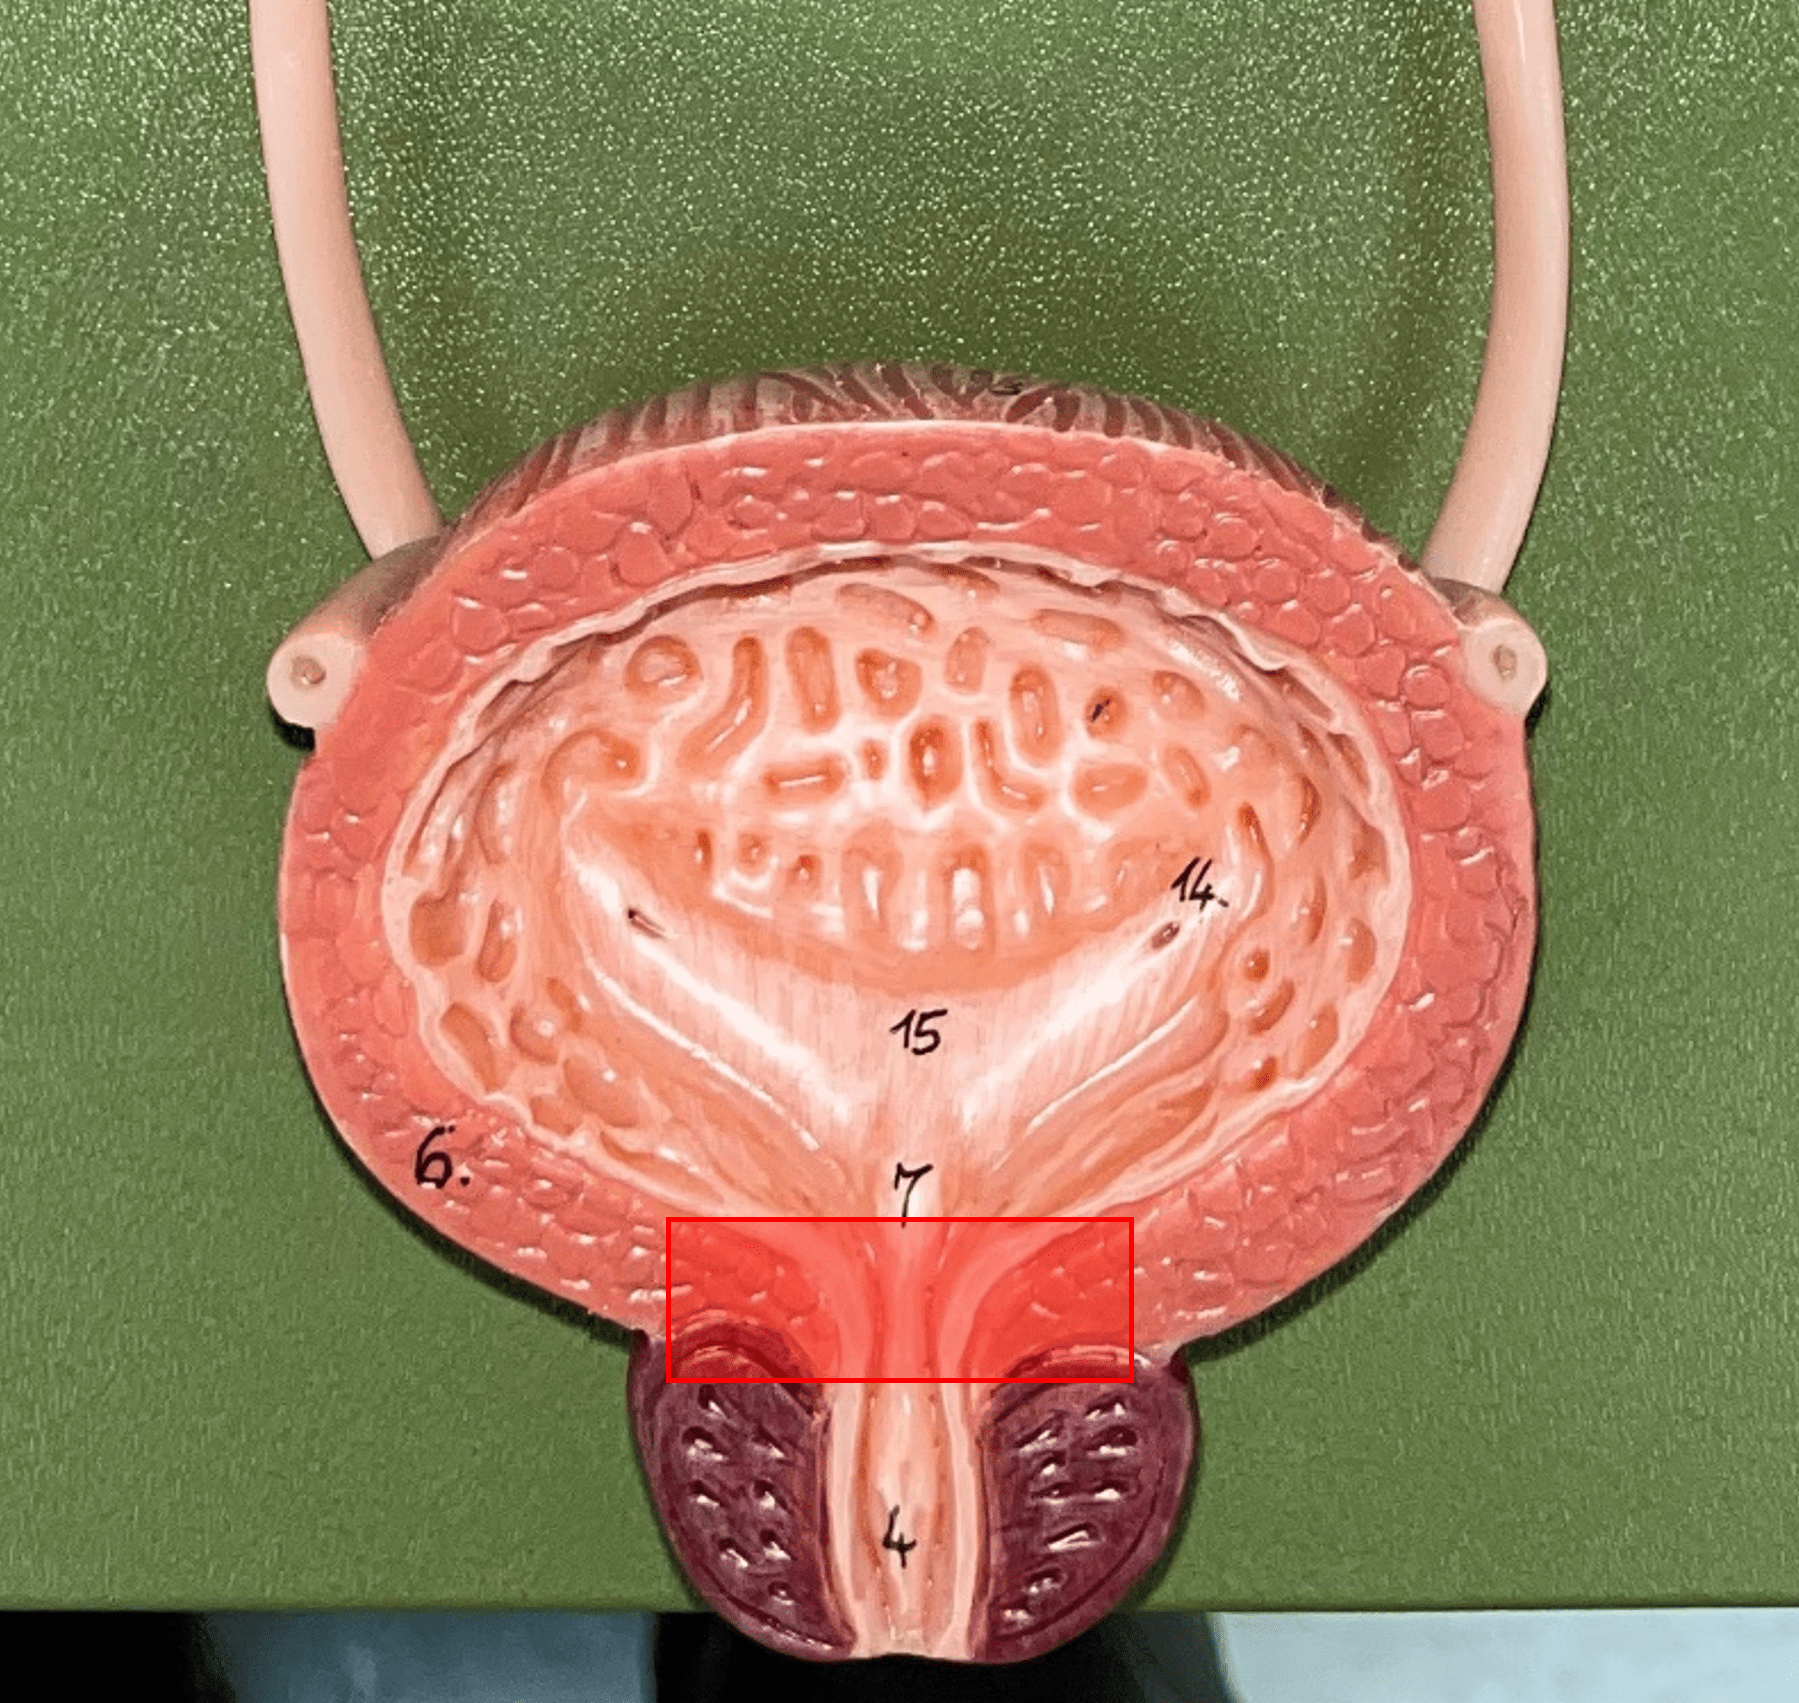

urinary bladder

The hollow sac organ that collects and temporarily stores urine.

rugae

• Part of the urinary bladder.

• Folds of the mucous membrane of the bladder.

• Flattens as the bladder fills with urine to increase capacity.

• Folds of the mucous membrane of the bladder.

• Flattens as the bladder fills with urine to increase capacity.

trigone

• Part of the urinary bladder.

• The triangle formed by the ureteral openings and internal urethra orifice.

• The triangle formed by the ureteral openings and internal urethra orifice.

ureteral opening

• Part of the urinary bladder.

• A posterior opening on either side of the of the bladder led in by the ureters.

• A posterior opening on either side of the of the bladder led in by the ureters.

internal urethral orifice

• Part of the urinary bladder.

• The anterior opening of the bladder leading to the urethra.

• The anterior opening of the bladder leading to the urethra.

detrusor muscle

• Part of the urinary bladder.

• The muscularis of the bladder.

• Contracts to expel urine from the bladder.

• The muscularis of the bladder.

• Contracts to expel urine from the bladder.

urethra

A tubular organ carrying urine from the bladder to the exterior during micturition (voiding of urine).

internal urethral sphincter

\

• Part of the urethra.

• A circular layer of circular smooth muscle located just after the internal urethral orifice.

• Involuntary muscle allowing urine to flow outward.

• Part of the urethra.

• A circular layer of circular smooth muscle located just after the internal urethral orifice.

• Involuntary muscle allowing urine to flow outward.

external urethral sphincter

• Part of the urethra.

• A layer of skeletal muscle located just before the external urethral orifice.

• Voluntary muscle allowing urine to flow out to the exterior.

• A layer of skeletal muscle located just before the external urethral orifice.

• Voluntary muscle allowing urine to flow out to the exterior.